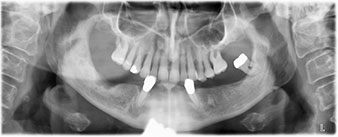

L’extraction de la denture résiduelle à la mandibule a exposé la crête alvéolaire de 37 à 47.

Le trou mentonnier doit d'abord être identifié comme une structure anatomique limitante, puis l'os cortical de la crête a été régularisé avec une pièce à main droite et une fraise sphérique de grande taille (Fig. 4).